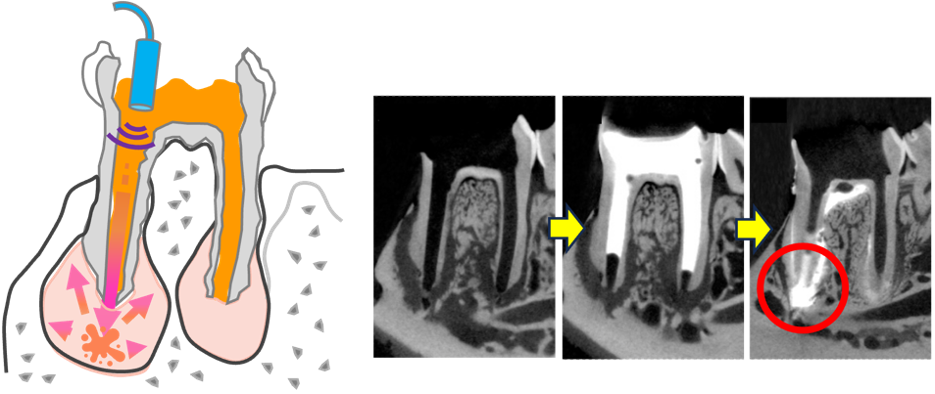

このような病態に対し、東北大学大学院歯学研究科の中野将人助教、Moe Sandar Kyaw助教、齋藤正寛教授、東北大学病院の田中志典講師らの研究グループは、なぜIBDにより顎骨破壊が増悪化するのかを明らかにするとともに、顎骨内で病的に活性化された炎症反応を抑制する新たな抗炎症治療技術の開発に取り組みました。具体的には動物モデルでAP単独の群、腸炎(Colitis)とAPを同時に発症させた群(Colitis+AP)の顎骨をマイクロCTという手法で歯の根の先端部分における骨破壊の体積を定量的に解析しました(図2)。その結果、AP単独では骨破壊範囲の体積は平均で0.2mm3ほどとなった一方、腸炎(Colitis)を伴う根尖性歯周炎群(Colitis+AP)では骨破壊範囲の体積が平均で0.6mm3ほどと増加し、歯の根の先端部における骨破壊が著しく増悪化し、臨床現場で観察されている病態が再現されたことを確認しました。さらに、このモデルを用いた解析から、好中球と呼ばれる免疫細胞が異常に活性化していることを見出すとともに、キャビテーションを用いて、根管から好中球の活性を抑制する抗炎症薬剤を顎骨へ直接浸透させる新規局所投与技術を開発し(図3)、顎骨破壊の進行を抑制できることを報告しました。